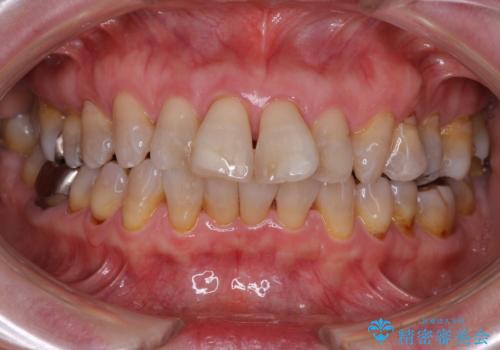

掃除しにくい前歯と閉じにくい口元 目立たないワイヤー装置での抜歯矯正